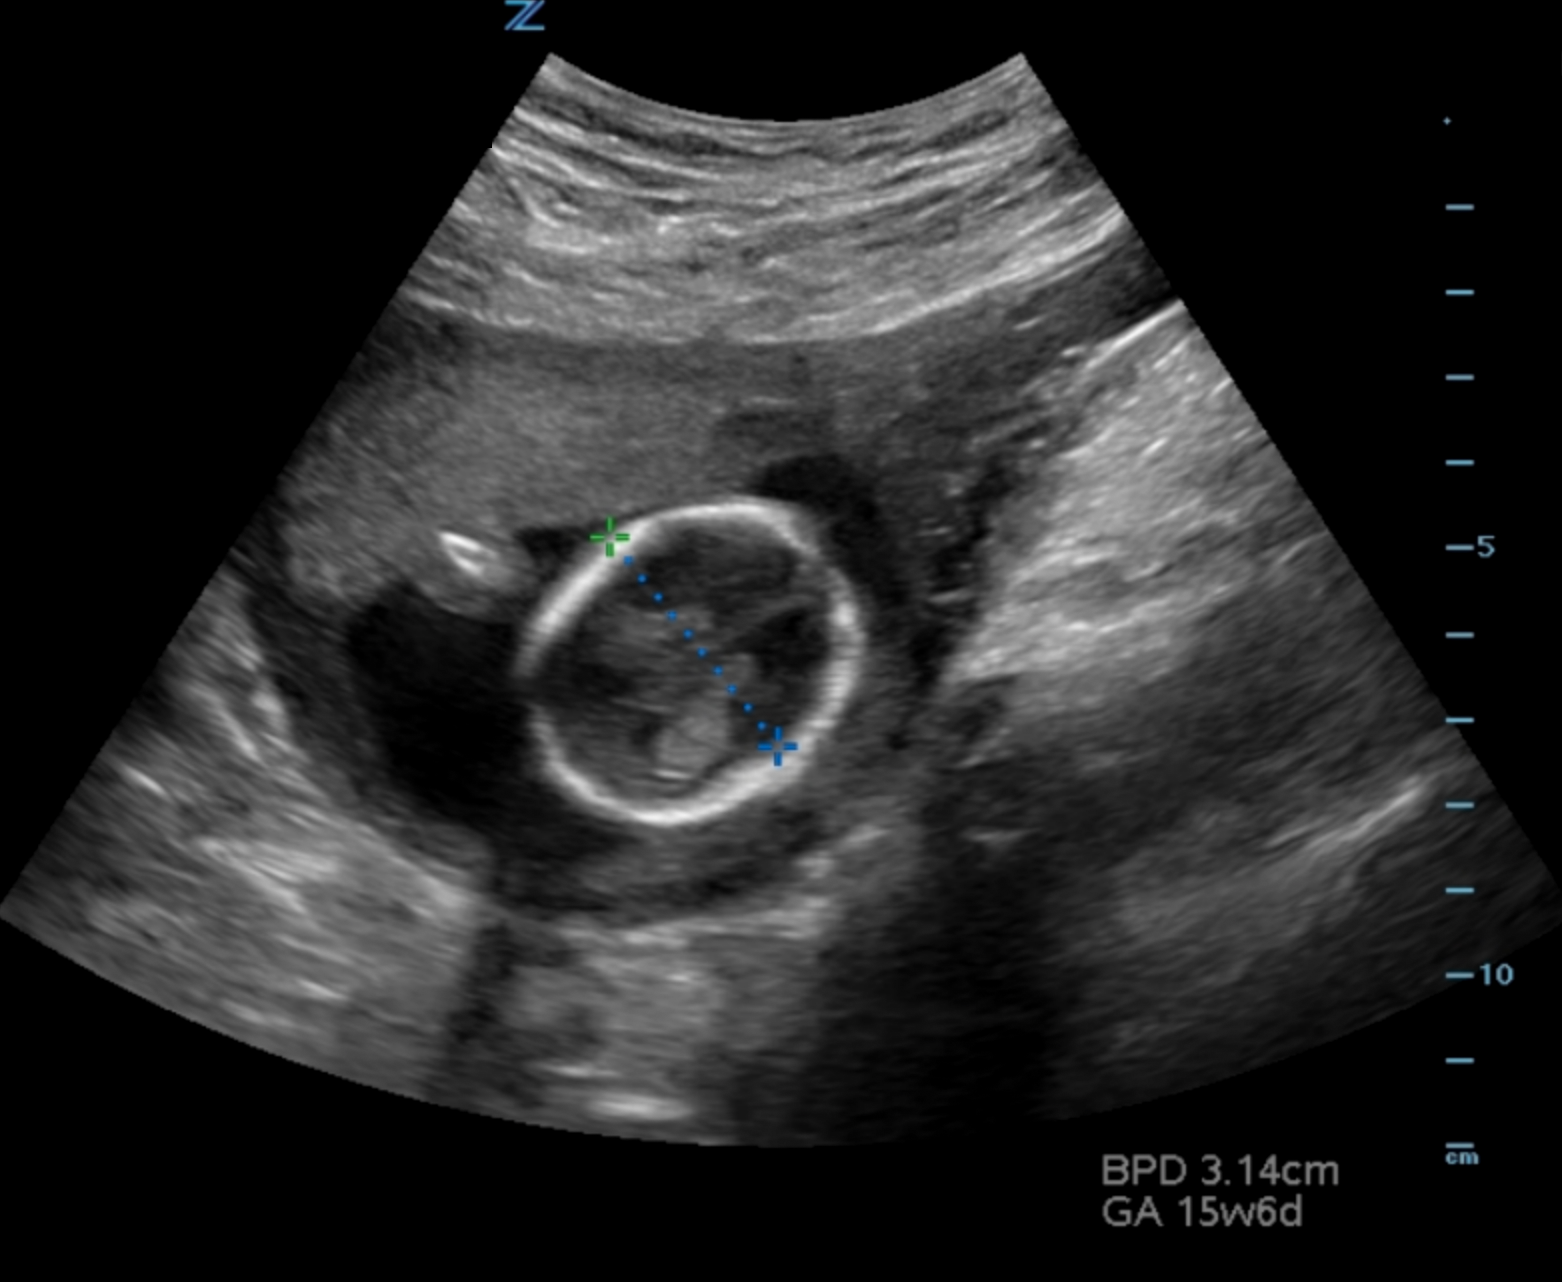

- Dating can be achieved by obtaining crown rump length when fetal pole becomes visible and then biparietal diameter when fetal skull becomes evident at the end of the first trimester.1 (Illustration 10, 11)

- Illustration 11. Transabdominal transverse view of 15-week fetus with biparietal diameter measurement from leading outer skull (most near field) to inner skull (far field) at the level of the ventricles.